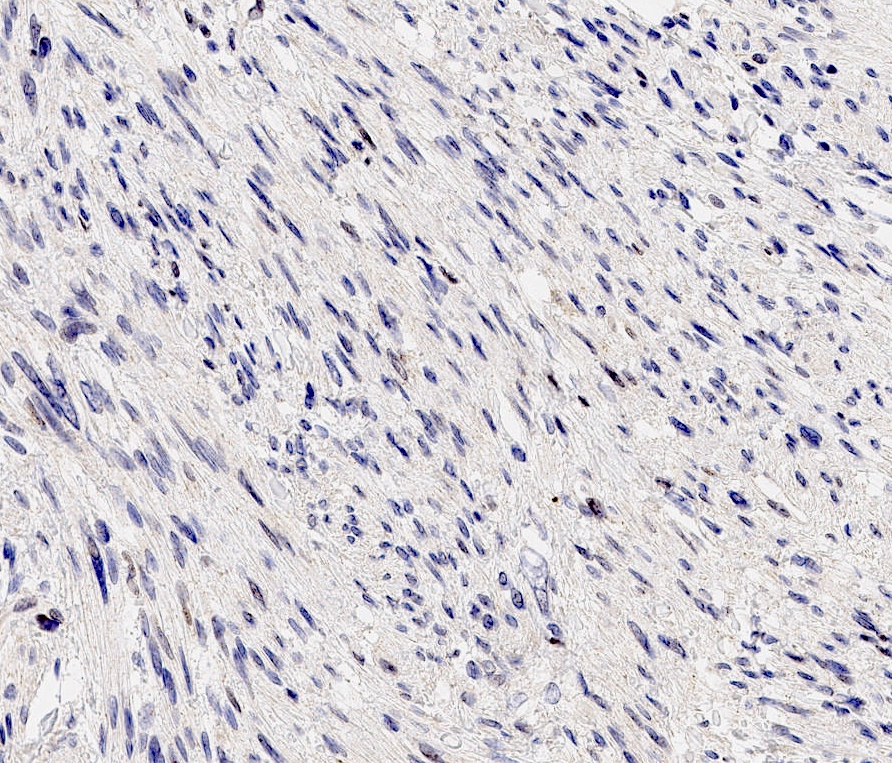

Microscopic (histologic) images

Negative stains

- Rb (negative in 89 - 92%) (Am J Surg Pathol 2016;40:361, Am J Surg Pathol 2012;36:1119)

- Actin (negative in 63%)

- Cytokeratins, S100, p63